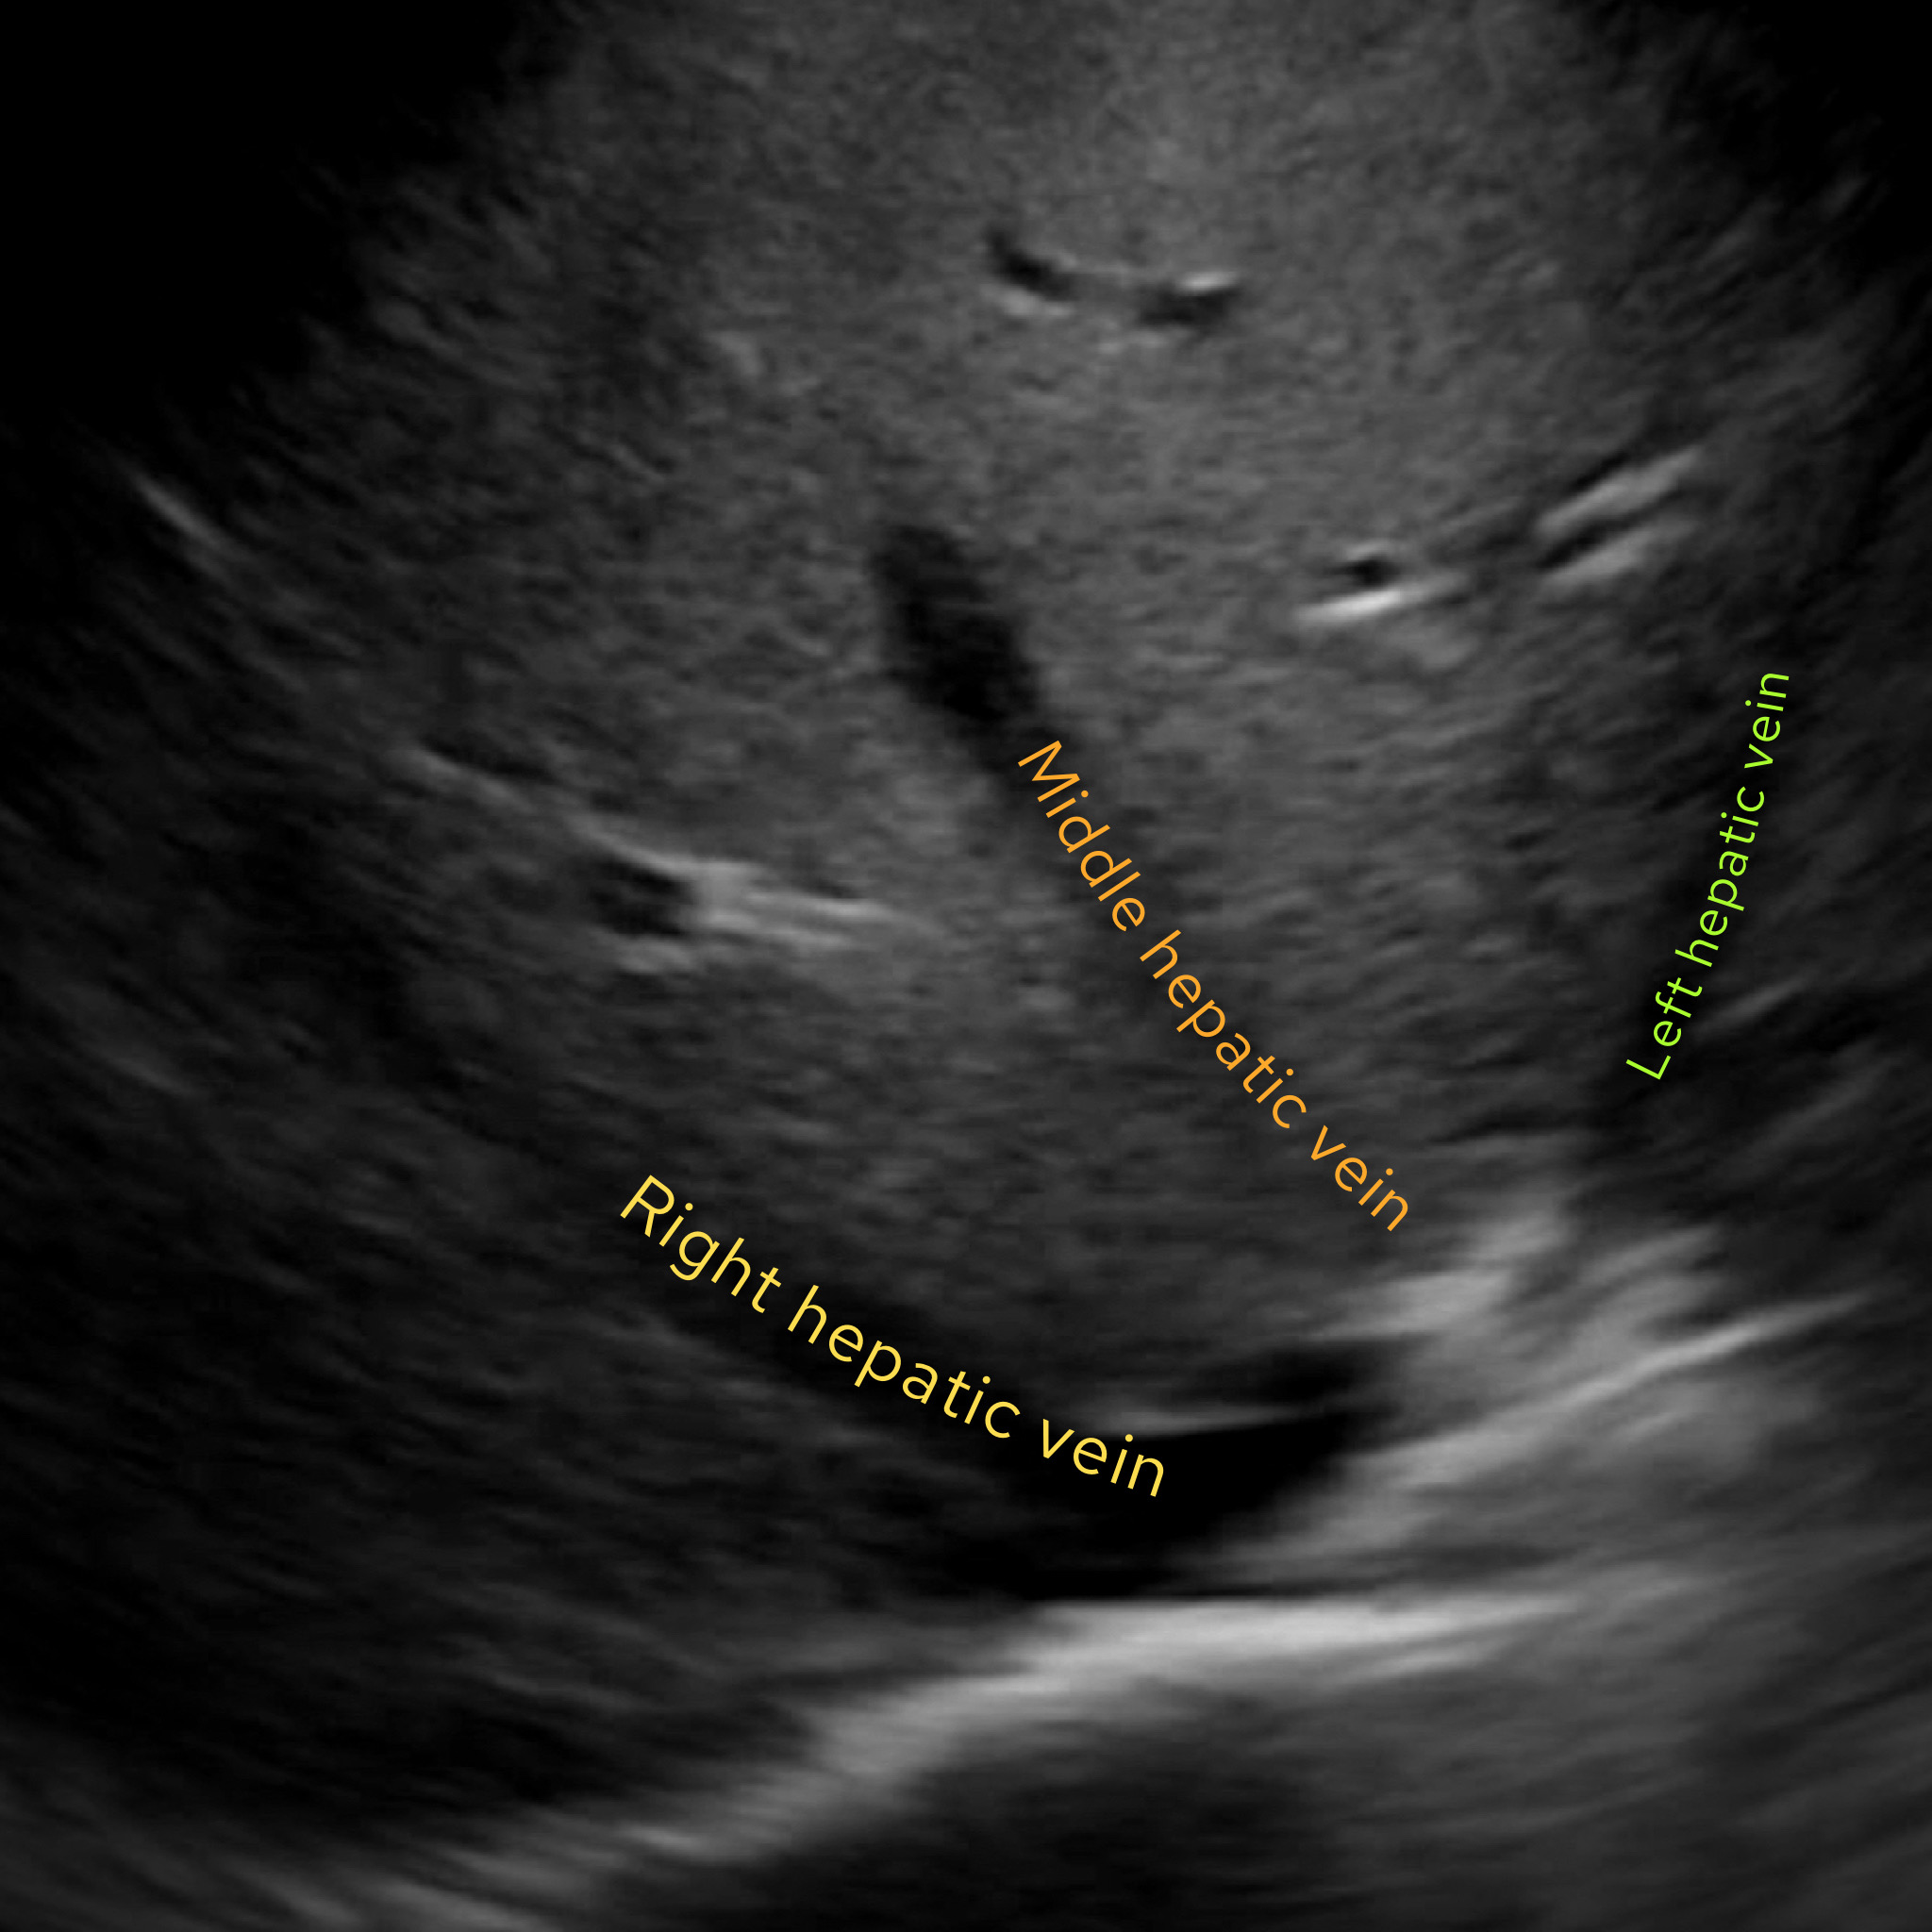

Case 6

This time we’re going to look at an ultrasound. What is the arrow pointing at here?

Answer: Right hepatic vein

This is an image of an ultrasound of the liver. We are near the top end (superior) of the liver. How do we know this? We can see the hepatic veins – these drain into the inferior vena cava at the superior end of the liver.

The hepatic veins drain into the inferior vena cava at the superior end of the liver

This image is a nice depiction of the hepatic veins and an image I try and see every time I do a liver ultrasound. I get the picture by placing the probe under the right costal margin (below the ribs anteriorly) and asking the patient to take a gentle but deep breath in before holding. I then fan through looking to find this picture. Don’t forget to let your patient breathe again or you’ll need to set off the crash alarm.

The three hepatic veins look a bit like ‘crow’s feet’ and can be easily distinguished as right, middle and left.

The three hepatic veins look like ‘crow’s feet’ heading towards the inferior vena cava